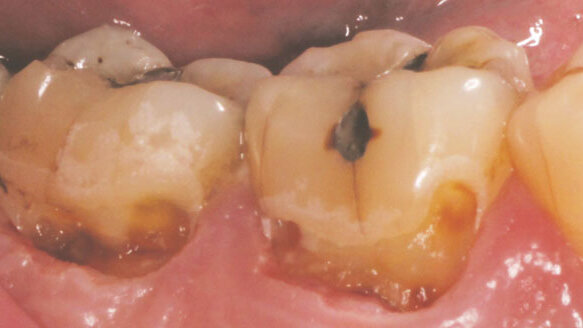

The patient presented with recurrent subgingival buccal decay on tooth #18 and #19 (B) (Fig. 1). The clinical objective was to completely remove the caries and then restore the teeth. The total procedure was completed in approximately 10 minutes and did not require any injectable anesthetic.

The dentin was now exposed, and I was ready to eliminate the deep decay (Fig. 4). For the decay removal in the dentin, the same 1.00 mm spot size was chosen with a cutting speed between 30–40 percent. The decay was then thoroughly and easily removed using the laser by applying a gentle gliding back-and-forth motion of the handpiece. Both teeth were then ready for restorative work using only the Solea and a spoon excavator.